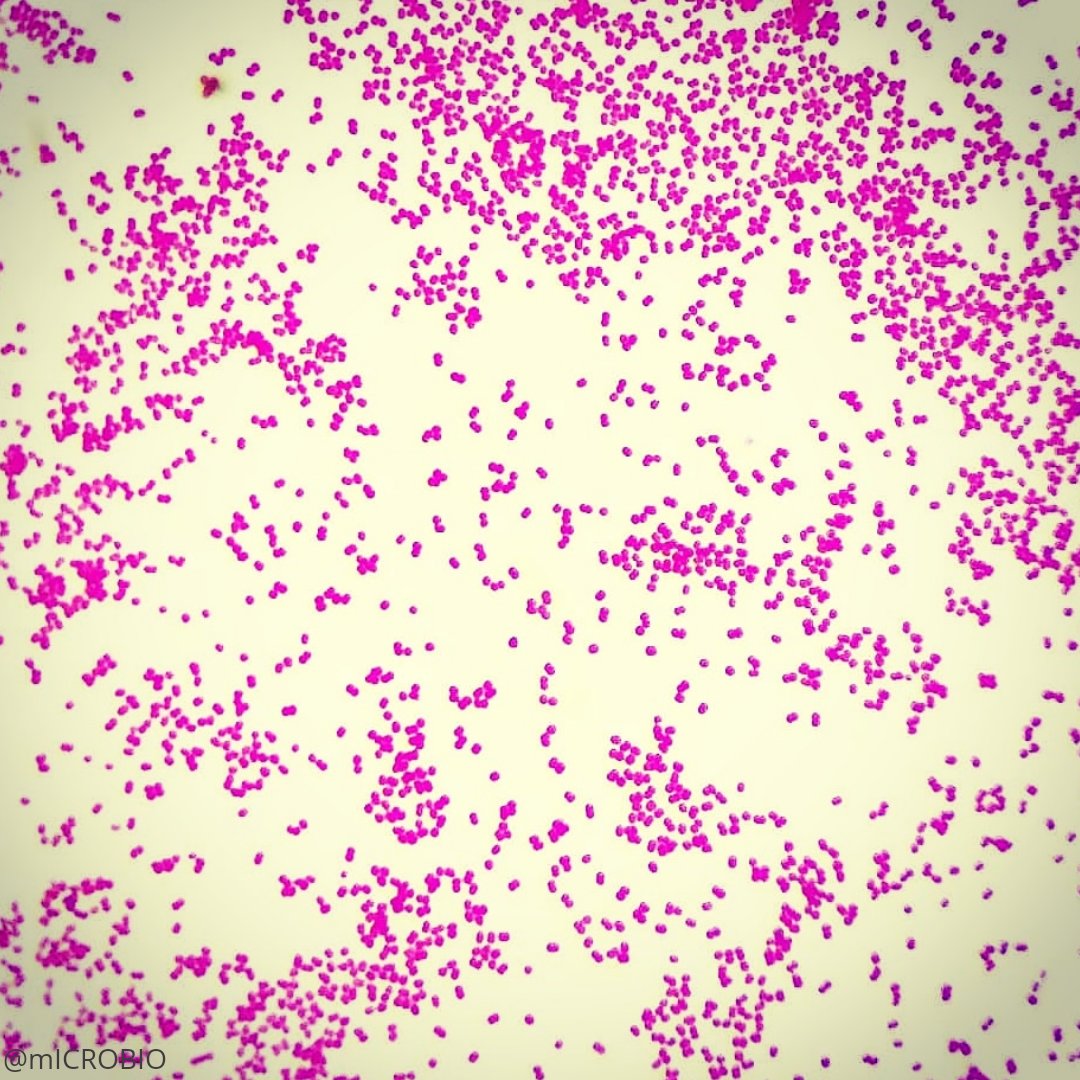

Gardnerella vaginalis

Esta enfermedad es producida por varias bacterias; de ellas, la más conocida es la Gardnerella vaginalis, también llamada Haemophilus vaginalis. Esta bacteria pertenece a la familia de los Bifodobacterium.

En caso de duda se puede efectuar un frotis, que consiste en tomar una muestra y analizarla al microscopio. También se puede realizar un cultivo. Existe adicionalmente una prueba sencilla: se agrega hidróxido de potasio a una muestra de la secreción; si la gardnerella está presente, despedirá un olor a pescado característico.